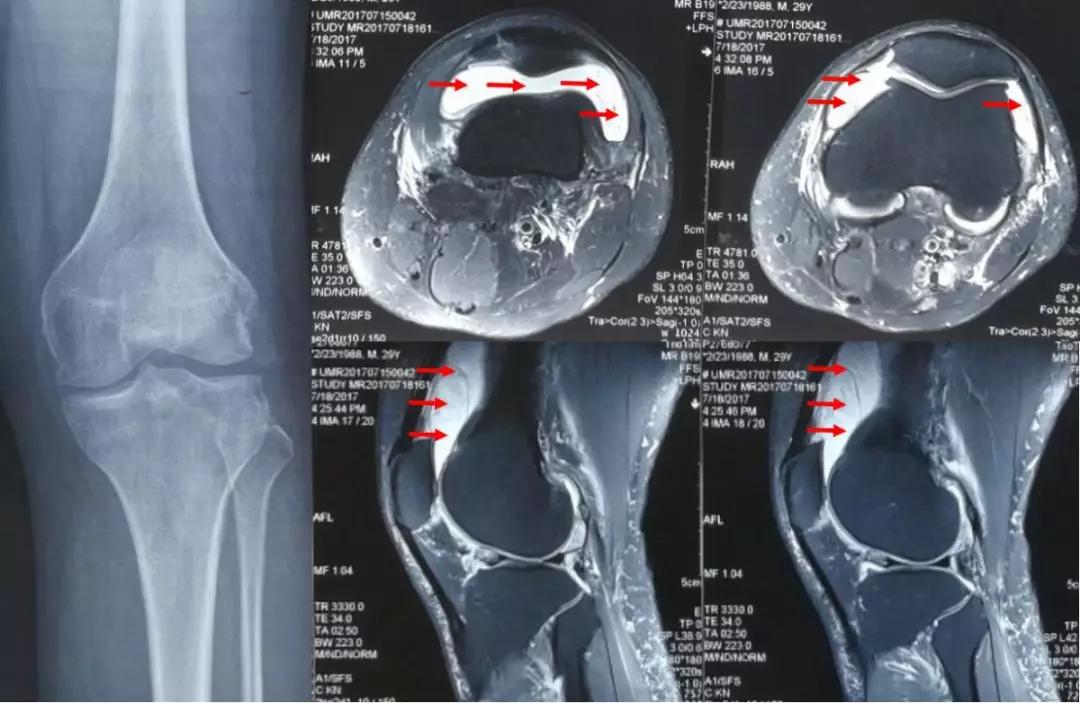

部分运动员因为炎症严重可以表现为膝外侧广泛的疼痛,甚至休息的时候也有疼痛。核磁共振检查可以看到髂胫束在膝关节部位增厚、水肿、积液,有助于确诊。